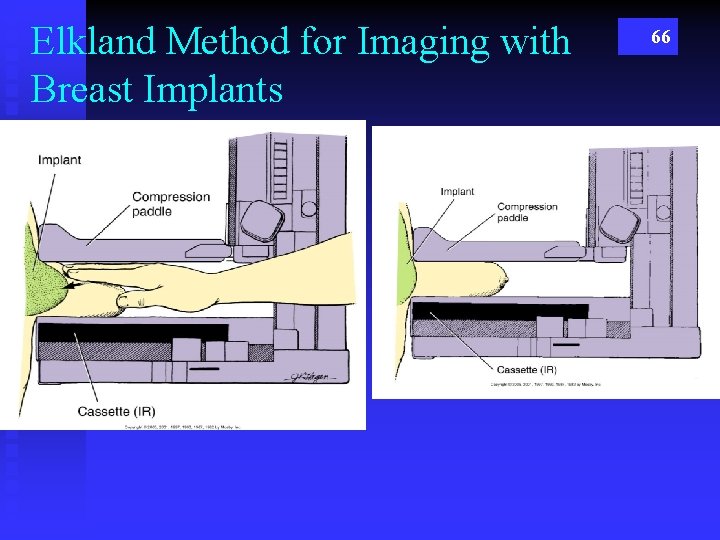

Elkland Method for Imaging with Breast Implants 66